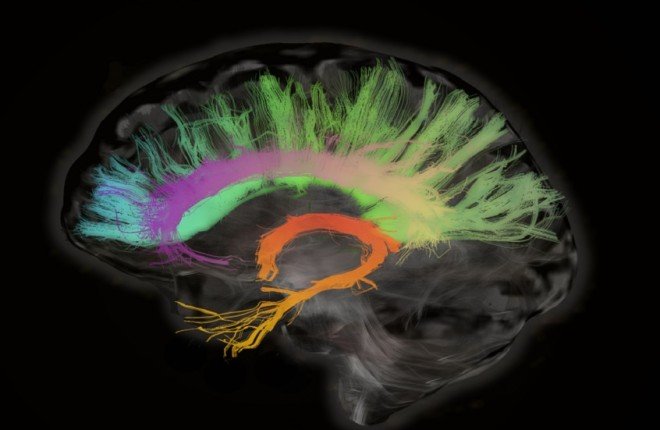

ثورة علمية تكشف أسرار الذاكرة.. آليات جديدة قد تعيد الشباب للدماغ!

في إنجاز علمي لافت، كشف فريق من جامعة فرجينيا للتكنولوجيا الأمريكية عن آليات جزيئية جديدة يمكنها تحسين الذاكرة مع التقدم في العمر، وفتح الباب أمام علاجات مبتكرة لمشكلات فقدان الذاكرة ومرض ألزهايمر.

الفريق، بقيادة البروفيسور تيموثي جارومي من كلية الزراعة وعلوم الحياة، توصّل إلى أن الشيخوخة ليست السبب الوحيد وراء ضعف الذاكرة، بل هناك تغيرات دقيقة داخل خلايا الدماغ يمكن التحكم فيها وتعديلها لإعادة تنشيط القدرات الإدراكية.

في الدراسة الأولى المنشورة في مجلة Journal of Neuroscience، ركز الباحثون على آلية تسمى "تعدد يوبيكويتين K63"، وهي المسؤولة عن تنظيم البروتينات داخل خلايا الدماغ وتنسيق عملها أثناء تكوين الذكريات.

وأظهرت النتائج أن هذه العملية تتأثر بشكل مختلف حسب منطقة الدماغ:

في منطقة الحصين (مركز تكوين الذاكرة): تزداد مستويات K63 مع التقدم في العمر، لكن خفضها بتقنية تعديل الجينات CRISPR-dCas13 حسّن ذاكرة الفئران المسنة بشكل مذهل.

أما في اللوزة الدماغية (المسؤولة عن الذاكرة العاطفية)، فانخفضت مستويات الآلية مع العمر، وكان تقليلها أكثر يؤدي إلى تحسين الأداء الذهني.

ويقول جارومي: “أثبتنا أن لآلية K63 دورًا مزدوجًا، ويمكن لتعديلها بدقة أن يُعيد للدماغ قدرته على تذكّر الأحداث حتى في مراحل الشيخوخة.”

إعادة تنشيط “جين الذاكرة” IGF2

وفي دراسة ثانية نُشرت في Brain Research Bulletin، اكتشف العلماء أن جينًا يسمى IGF2، المسؤول عن بناء الذاكرة، يُغلق تدريجيًا مع التقدم في العمر بسبب تغييرات كيميائية تعرف بـ “ميثلة الحمض النووي”.

وباستخدام أداة تعديل الجينات الدقيقة CRISPR-dCas9، تمكن الفريق من إزالة العلامات الكيميائية التي عطّلت الجين، ما أعاد تنشيطه ونتج عنه تحسن ملحوظ في ذاكرة الفئران المسنة.

وأكد جارومي أن هذا الجين ينشط من نسخة واحدة موروثة من أحد الأبوين، ومع فقدانها تتراجع الذاكرة، لكن إعادة تشغيله تعيد الدماغ إلى أداء شبابه.

نحو فهم شامل لشيخوخة الدماغ

ويشير العلماء إلى أن فقدان الذاكرة لا يرتبط بمسار واحد، بل هو نتيجة تفاعل معقد بين عدة أنظمة جزيئية في الدماغ، ما يعني أن علاج الشيخوخة الإدراكية يحتاج إلى رؤية شاملة تتجاوز التركيز على جزيء واحد أو دواء واحد.

“نحن نقترب من مرحلة يصبح فيها تحسين الذاكرة في الشيخوخة أمراً ممكناً علمياً، ليس فقط عبر الأدوية، بل من خلال إعادة برمجة الخلايا العصبية نفسها.”

اكتشاف قد يغير مفهوم الشيخوخة الإدراكية بالكامل، ويفتح الطريق أمام جيل جديد من العلاجات التي تُعيد للدماغ ذاكرته وحيويته.